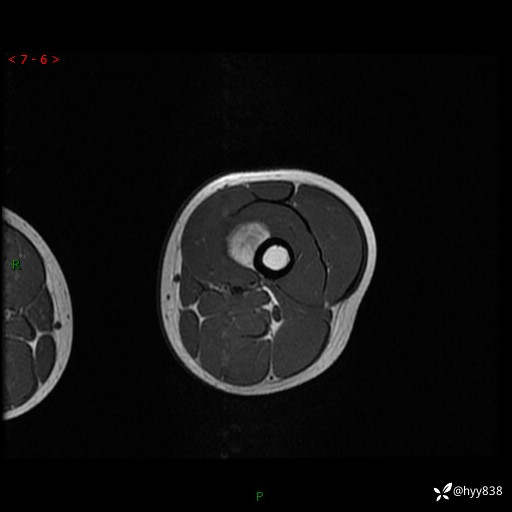

现病史:患儿3天前无意中被发现其左大腿有一包块,约鸡蛋大小,包块表面皮肤无红肿、触痛,无发热、破溃等,患儿家属当时未做特殊处理,经观察发现包块未见消退,今携患儿来我院就诊,门诊医师以“左大腿包块”收入院。 病程中,患儿神清,精神可,饮食睡眠正常,大小便通畅,体力体重无明显改变。

左大腿MRI平扫+增强